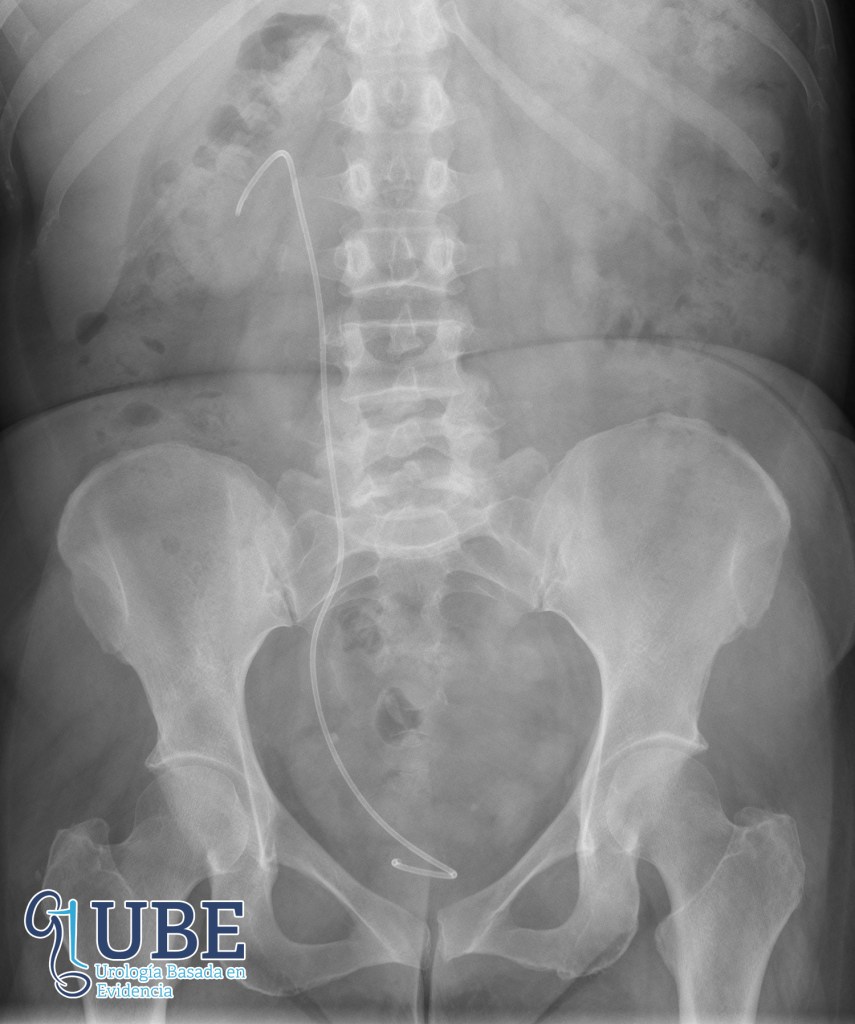

Un catéter doble J es un tipo de tubo hueco y flexible que mide aproximadamente unos 26 a 30cm de largo y unos 2mm de grosor, habitualmente hecho de poliuretano o silicona aunque los hay de otros materiales.

Suele insertarse endoscópicamente (a través de la uretra se accede a la vejiga con una cámara), dicha camara se denomina cistoscopio, el cual puede ser flexible o rígido, el catéter se asciende de forma retrógrada hasta el riñón, habitualmente bajo control radiologíco con un fluoroscópio para verificar intra-operatoriamente la correcta posición del catéter.